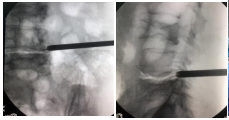

经刘鹏副主任医师主刀,在陈浩主治医师、关健斌医师的协助下,手术顺利完成。术中局麻效果满意,采用侧方入路穿刺于椎间孔外口,镜下可见椎间孔黄韧带增生,椎间孔重度狭窄,采用镜下环锯去除少量腰5上关节突腹侧骨质,充分去除增生黄韧带,对腰4出口根及腰5行走根减压,仅用时半小时就完成手术。术后即刻,闫老太太便觉得轻松许多,流露出欣慰的笑容,当晚便自己下地行走。